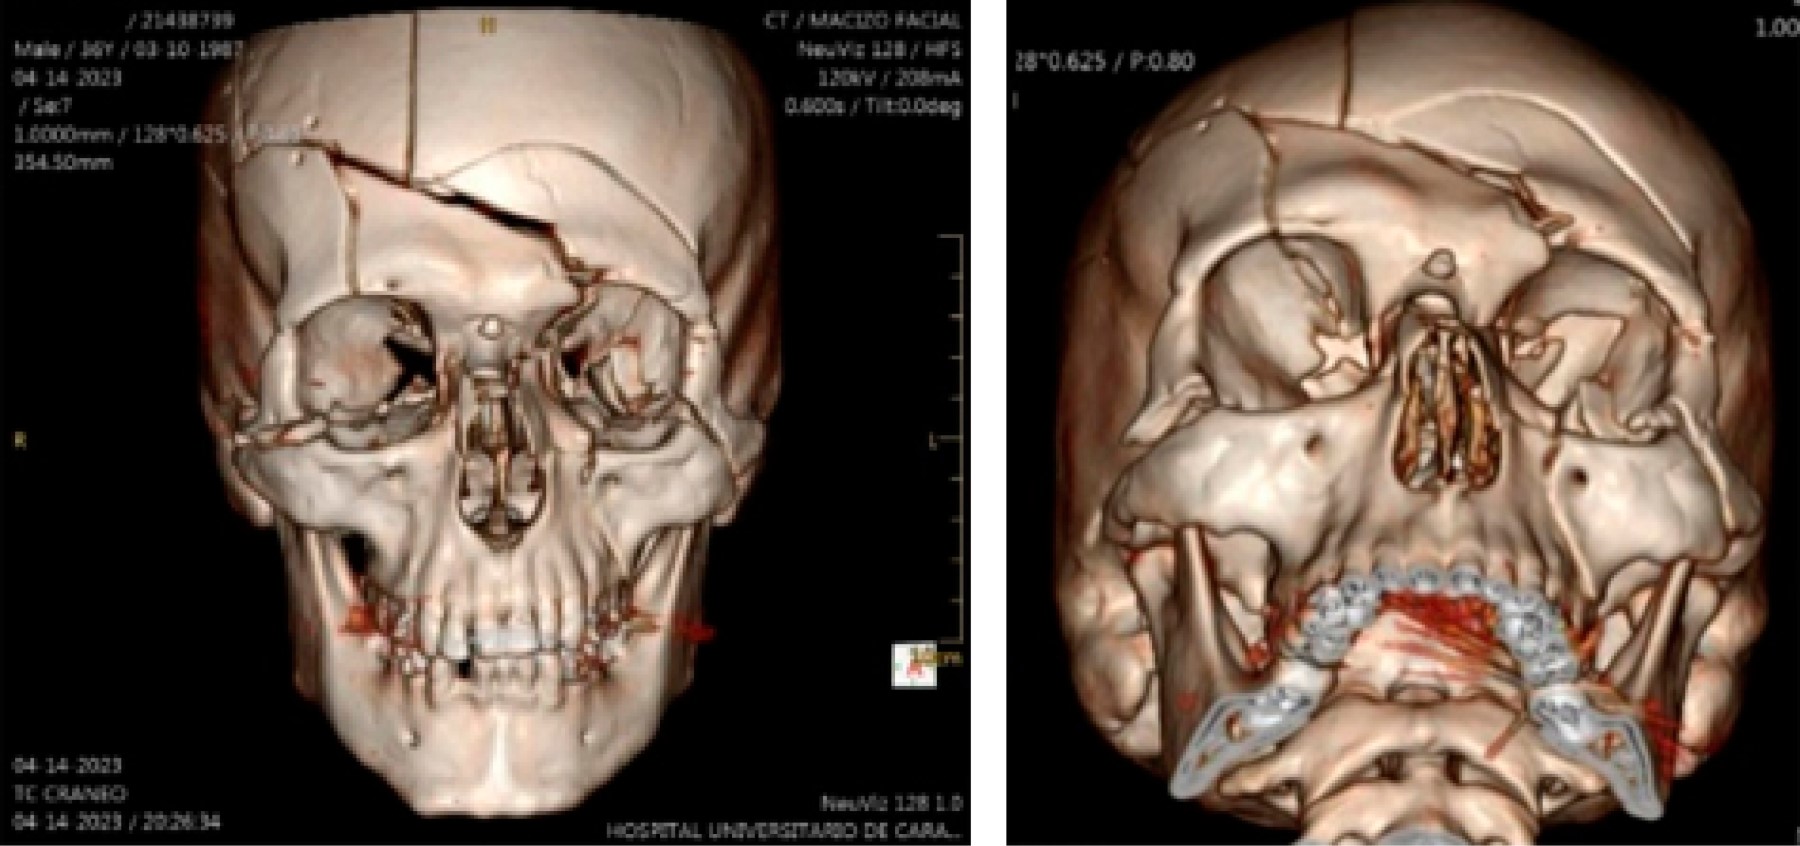

Se trata de paciente masculino de 37 años, sin antecedentes médicos conocidos, quien llega al Servicio de Emergencia del Hospital Universitario de Caracas posterior a sufrir politraumatismo por accidente en vehículo en movimiento tipo moto en calidad de piloto. Es evaluado por el Servicio de Emergencia para control de la vía aérea y columna cervical, respiración, circulación, valoración del estado neurológico y exposición y control ambiental (ABCDE), tomografía computarizada (Figuras 1 y 2) y posteriormente realizan síntesis de tejidos de heridas lacerantes en región facial. Es llevado a mesa operatoria para realizar traqueotomía, drenaje de hematoma epidural y colocación de ivy loops y posteriormente ingresado en la Unidad de Cuidados Intensivos para estabilización y control. Al examen maxilofacial presentó equimosis bipalpebral bilateral, puntos de sutura en región frontal bilateral que discurren a párpado superior izquierdo, puntos de sutura en región infraorbitaria izquierda, región nasogeniana izquierda, heridas dermoabrasivas en región frontal bilateral, dorso y punta de la nariz, región infraorbitaria izquierda, nasogeniana izquierda y región mentoniana; al examen intraoral apertura bucal limitada, edentulismo parcial bimaxilar, hematoma en fondo de vestíbulo superior izquierdo y mucosa yugal izquierda, puntos de sutura en fondo de vestíbulo izquierdo, fijación intermaxilar con ivy loops y movilidad de OD 1.2.

Figura 1

Figura 2

La tomografía computarizada (TC) con reconstrucción volumétrica 3D se ha vuelto el estándar de oro en examen imagenológico para pacientes con trauma en la región facial, ya que presenta información 1:1 del patrón de fractura.4

La tomografía computarizada (TC) con reconstrucción volumétrica 3D es el examen imagenológico de elección para evaluar el patrón de fractura en pacientes con trauma facial. Proporciona información detallada y precisa sobre las fracturas, lo que permite una mejor planificación quirúrgica. En este caso, se utilizó una TC postoperatoria para evaluar los resultados de la cirugía.9